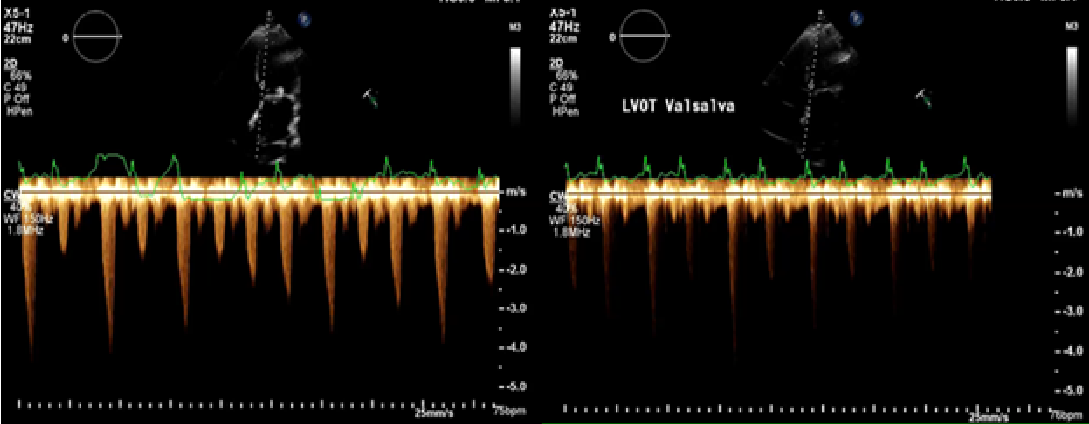

Due to ongoing clinical symptoms, he was then referred to our Interventional Cardiology team for a second opinion. A transthoracic echocardiogram on initial visit revealed severe LVOT obstruction which worsened with the Valsalva maneuver (peak velocity>4.5m/s) with a mean gradient across the mitral valve of 10mm Hg (Figure 2). Now post-TMVR, gatedchest computed tomography (CT) scan revealed evidence of the prosthetic mitral valve encroaching on the LVOT with small neo-LVOT, systolic anterior motion (SAM) of the native anterior mitral leaflet and persistent iatrogenic atrial septal defect with continuous left-to-right shunt (video 4). Left & right heart catheterization revealed neo-LVOT obstruction (baseline gradient 15-20mmHg) with a post-PVC gradient of 80mmHg and low cardiac index of 1.7L/min/m2. In addition, there was now an evidence of elevated gradient across mitral valve (mean of 10mmHg) on TEE as well as on cardiac catheterization assessment. Due to complex current clinical scenario including elevated trans-mitral gradients concerning for malfunctioning bioprosthesis, patient underwent a redo sternotomy with a 31mm St. Jude mechanical mitral valve replacement successfully. Intra-operatively, incomplete expansion of the Sapien 3 valve was noted causing altered leaflet mobility being the likely cause of elevated gradient across the bioprosthesis on pre-operative TEE. Post-op, the patient had a complete resolution of his symptoms.

Figure 2 Respirophasic changes in LVOT velocity (panel A) and increased gradient with Valsalva (panel B) showing peak velocity of 4.5m/s.